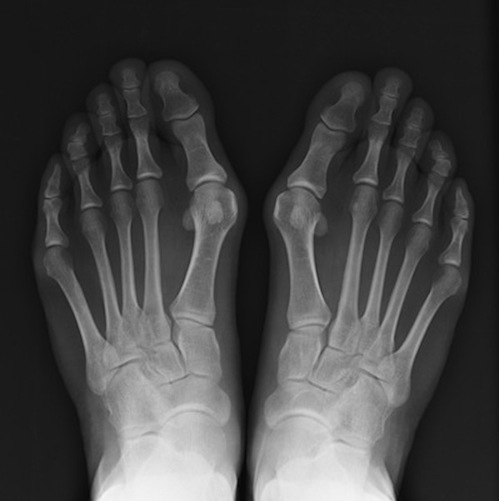

L'alluce valgo nell'immaginario comune è un problema soprattutto di natura estetica, ma nella realtà è una patologia assai più grave e dolorosa.

In sostanza la sporgenza dell'alluce valgo altro non è che la testa del primo metatarsale, ovvero l'osso sul quale si articola la falange del primo dito del piede, con sporgendo verso l'esterno con il npassare del tempo provoca l'infiammazione dei tessuti circostanti.

Lo slittamento del metatarsale speso si accompagna alla deviazione dell'alluce verso le altre dita, deformando anche le stesse.